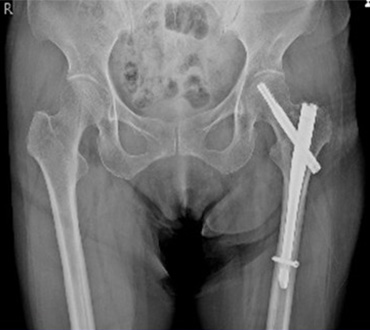

一般撮影室

主にレントゲン写真と呼ばれていてX線を利用し、胸部、腹部、骨などの撮影をします。人体にX線をあて透過したX線をコンピュータで処理し画像にします。迅速に画像を提供できることから、日常の診断に最も多く利用されている検査です。

人体を透過したX線をモニターでリアルタイムに見ることができます。造影剤(バリウムなど)を使用する胃、腸の検査のほか、骨折の整復、内視鏡を用いての胆管結石の除去、腸閉塞の時にお腹にチューブを入れる検査等に使用しています。